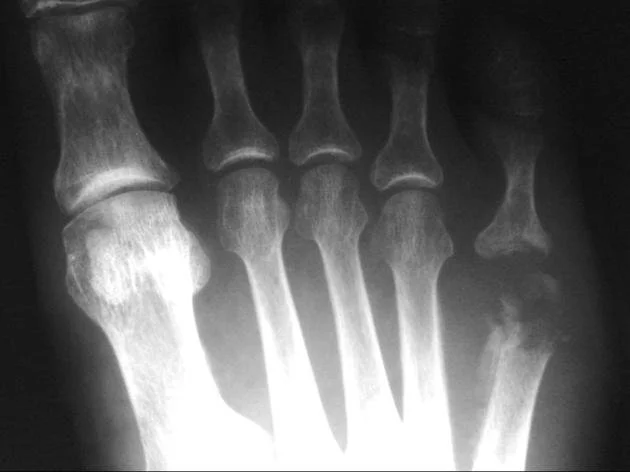

• 🧲 MRI – The gold standard because X-rays are like “I’ll show something… in a few weeks maybe.” There is typically a lag of about 10-14 days. Don’t wait by the phone.